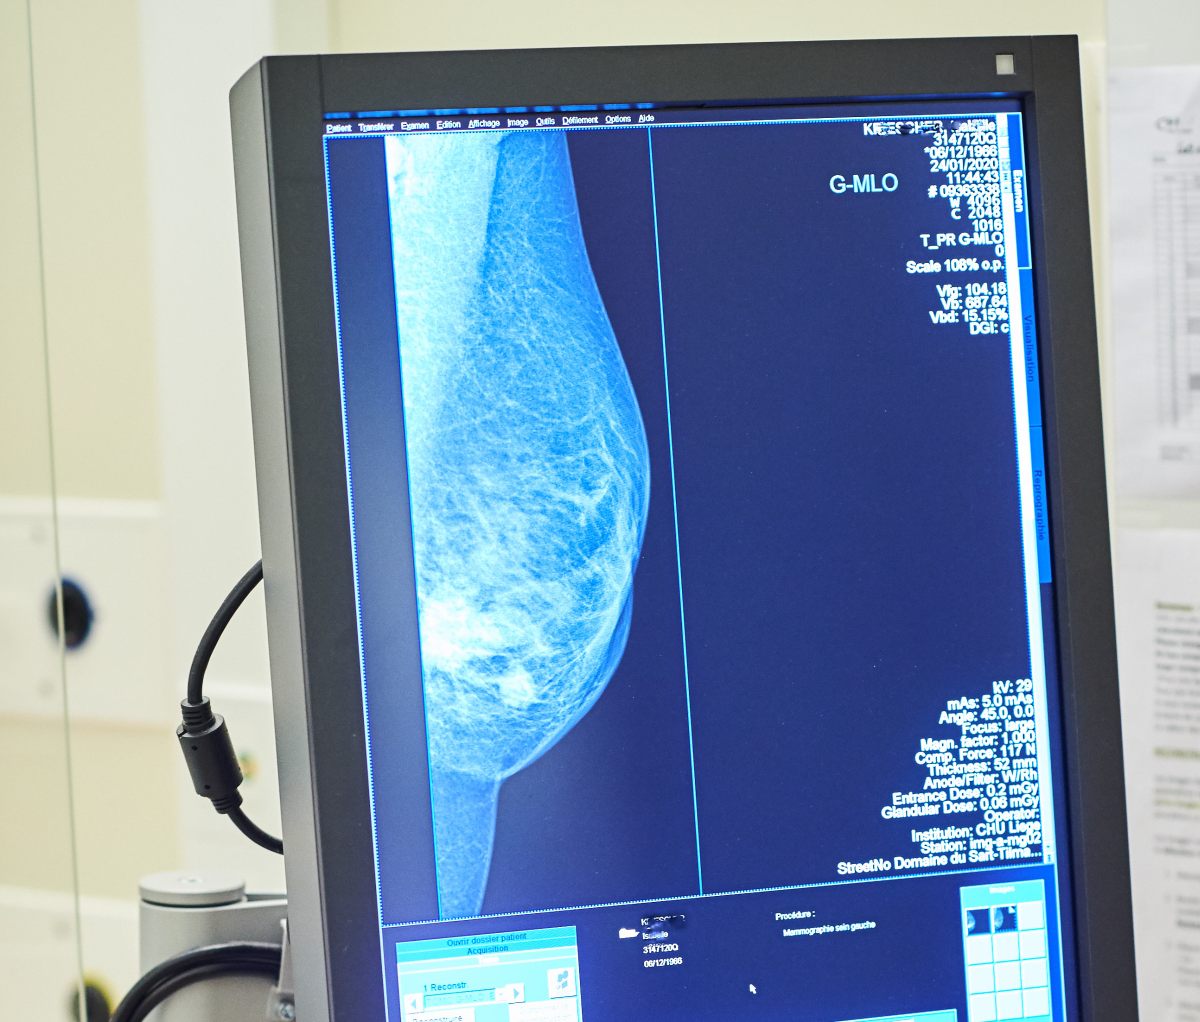

MAMMOGRAFIA DIAGNOSTICA PREVENZIONE CANCRO TUMORE RADIOGRAFIA ESEGUITA MENTRE IL SENO E